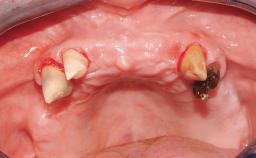

A 65-year-old female patient with a failing residual maxillary dentition and a complete mandibular removable denture was referred for consultation and treatment. The patient’s chief complaint was that her upper residual teeth were mobile and she was unable to chew. The patient also asked us to improve the esthetic appearance of her smile. The patient’s desire was a stable and comfortable dentition in both jaws, and she specifically asked for a fixed rehabilitation. The patient reported a history of recurrent caries, endodontic complications, and periodontal disease as main reasons for previous teeth extractions. The anamnesis was negative for bruxism and TMJ disorders. The patient had no systemic diseases, was not on any medication,and did not smoke. The extraoral examination revealed a medium lip line, a wide diastema between the two central incisors (which, according to the patient, had appeared recently), and a partial collapse of the perioral soft tissues, probably due to loss of the correct vertical dimensions.